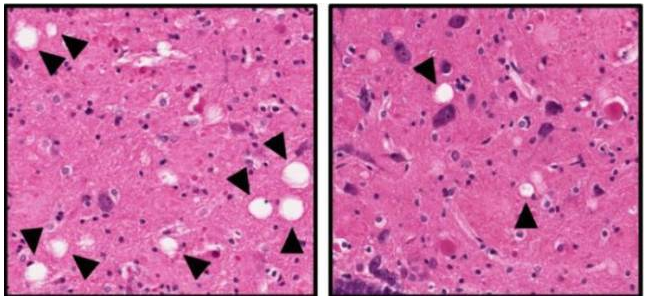

安慰剂大鼠(左)大脑出现了严重的神经损伤(箭头所指空泡代表坏死的神经组织)而接受 P7C3 治疗的大鼠损伤显著降低(右)

不仅如此,当 Pieper 教授在 24 个月时对两组大鼠的大脑组织进行组织病理学检查以及淀粉样沉积物,Tau 蛋白磷酸化,神经炎症标志物检查。结果发现,P7C3 并没有改变大鼠脑内这些所谓的“阿尔兹海默病标志物”的堆积,即这些标志物在两组大鼠脑内的堆积状况是相同的。也就是说,即使存在早期的阿尔茨海默病病理事件,例如淀粉样蛋白积累,神经纤维缠结和神经炎症,P7C3 仍旧具有强大的保护神经损伤功能,并且这一治疗方案仍能带来明显的临床益处。